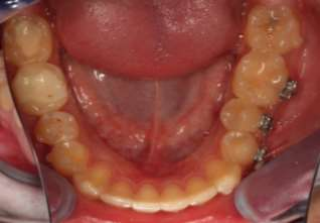

Fig. 1: Tooth 35 does not fit well with the aligners

Fig. 2: Fit problems in region 35